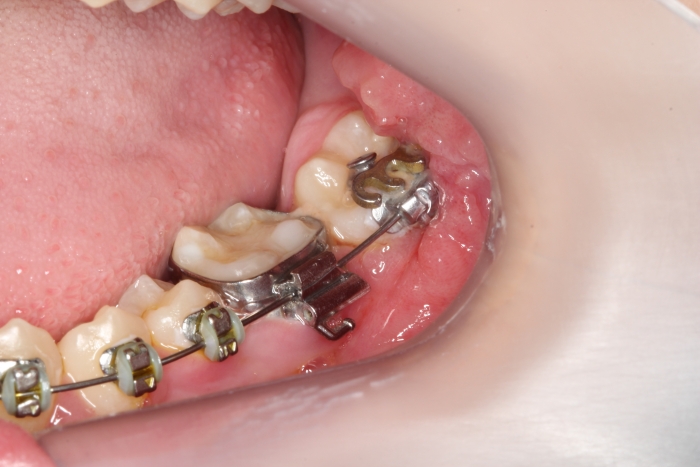

Dentes em tracionamento, imediatamente após a cirurgia - Clínica Cliniface

Dentes em tracionamento, imediatamente após a cirurgia